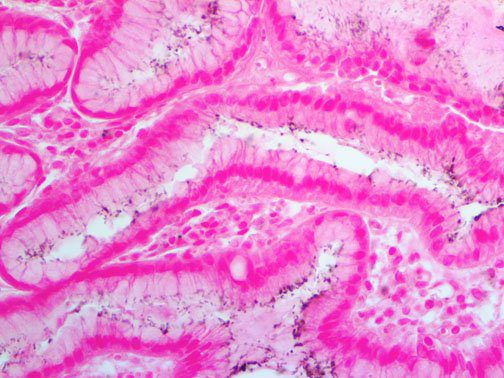

It is the ICU physician who is most likely to witness one of the deadliest manifestations of the abnormal immunological response, the cytokine storm syndrome (CSS). This response is also referred to by some as the cytokine release syndrome (CRS). CSS is characterized by continuous activation and expansion of macrophage and lymphocyte populations, which secrete large amounts of cytokines, causing the cytokine storm. This massive cytokine release is akin to hemophagocytic lymphohistiocytosis (HLH) disease, a syndrome characterized by initial unchecked and persistent activation of cytotoxic T lymphocytes and NK cells.

Clinical and laboratory manifestations of HLH include fever, enlarged liver and/or spleen, neurologic dysfunction, coagulopathy, liver dysfunction, cytopenias (i.e., low levels of erythrocytes, leukocytes, and/or platelets), hypertriglyceridemia, hyperferritinemia, hemophagocytosis, and eventually diminished NK cell activity as the immune system becomes progressively paralyzed. HLH can be familial (primary HLH) or secondary to another disease process (sHLH), such as rheumatic disease, in which it is referred to as macrophage activation syndrome (MAS, characterized by elevated ferritin).

This activation induces inflammatory monocytes to highly express IL-6, starting a localized and then systemic cascade effect that results in hyperproduction of IL-6, which accelerates the inflammatory process. Because IL-6 also increases vascular permeability, excessive levels cause blood vessels to become very leaky. This, along with clotting factors released from vascular endothelial cells, stimulates the coagulation cascade, resulting in microthrombosis (tiny clots), which leads to ischemia and tissue death of the kidney, intestines, heart, liver, brain and extremities.